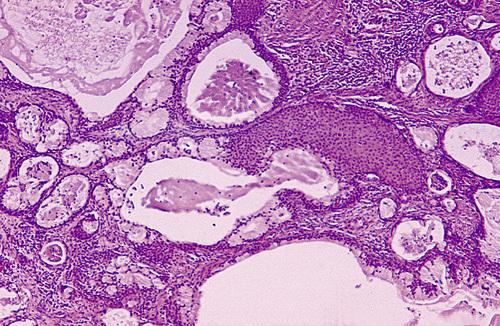

Islands of hyperchromatic cells forming cribriform and tubular structures. Inset shows a high-power view of a small cribriform island. The cribriform pattern is the most classic appearance, characterized cystlike spaces resembling Swiss cheese.

adenoid cystic carcinoma

The tumor cells are surrounded by hyalinized material. In the tubular pattern, the tumor cells are similar but occur as multiple small ducts or tubules within a hyalinized stroma.

adenoid cystic carcinoma

Perineural invasion. This is a highly characteristic feature of this tumor, probably corresponding to the common clinical finding of pain in these patients.

adenoid cystic carcinoma